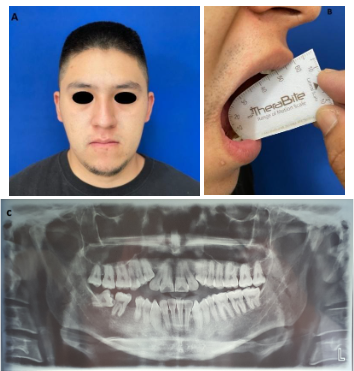

A los cinco meses, se practicaron controles postquirúrgicos clínicos e imagenológicos con una ortopantomografía en el servicio de Cirugía Oral y Maxilofacial del Hospital General “La Perla”, Nezahualcóyotl en el Estado de México. No se registraron signos de recurrencia de luxación de ATM y se encontró una adecuada posición de los cóndilos mandibulares en sus fosas articulares del hueso temporal (Ver Figura 6).